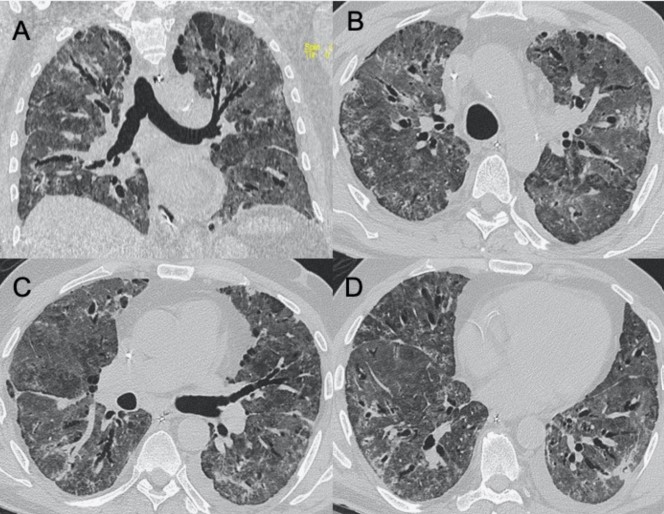

?HINI流感病毒

● CXR:單側(cè)/雙側(cè)GGO,伴或不伴實(shí)變區(qū)域,主要分布于支氣管血管周圍和胸膜下。

● CT:單側(cè)/雙側(cè)GGO,伴或不伴實(shí)變區(qū)域,主要分布于支氣管血管周圍和胸膜下。

圖4 圖(A-D)為一例H1N1相關(guān)肺炎并發(fā)急性呼吸窘迫綜合征(respiratory distress syndrome,ARDS)的影像,可見彌漫性和雙側(cè)GGO以及牽引性支氣管擴(kuò)張。